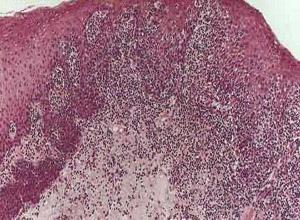

简介蕈样真菌病(mycosis fungoides,MF)是一种T细胞起源的恶性肿瘤,又称蕈样肉芽肿(granuloma fungoides),是一种向上皮性皮肤淋巴瘤。其特征为辅助T细胞增生,Langerhasns细胞和交指状网状细胞也参与病变。病程呈慢性渐进性,初期为多种形态的红斑和浸润性损害,以后发展成肿瘤,晚期可累及淋巴结合内脏。